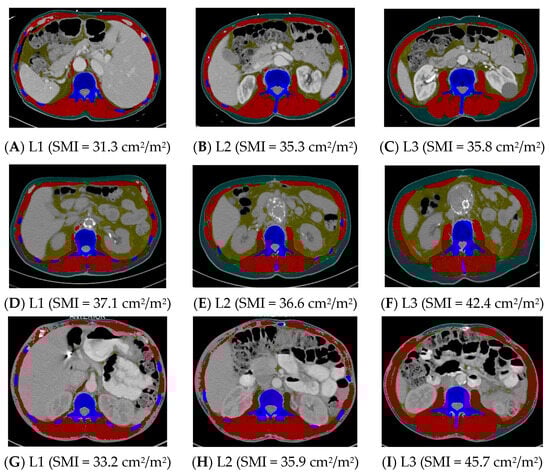

2.2. Assessing the Use of Alternative Vertebral Landmarks

5.3. Image Analysis

5.4. Primary Dependent Variables